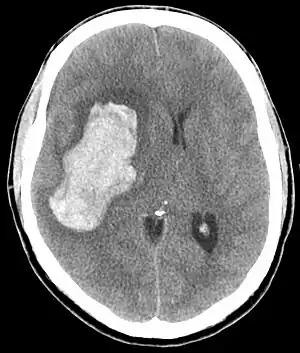

| CT scan of an intracranial bleed, a possible complication of a hypertensive emergency. | |

The most common presentations are stroke (25%), pulmonary edema (23%), hypertensive encephalopathy (16%), and heart failure (12%).[9] Less common include intracranial bleeding, aortic dissection, and pre-eclampsia or eclampsia.[10] The eyes may show hypertensive retinopathy (bleeding in the retina, an exudate, cotton-wool spots, scattered splinter hemorrhages, or swelling of the optic disc called papilledema).

In the brain, hypertensive encephalopathy - characterized by hypertension, altered mental status, and swelling of the optic disc - is a manifestation of the dysfunction of cerebral autoregulation. Cerebral autoregulation is the ability of the blood vessels in the brain to maintain a constant blood flow. People with chronic hypertension can tolerate higher arterial pressure before their autoregulation system is disrupted. Hypertensives also have an increased cerebrovascular resistance which puts them at greater risk of developing cerebral ischemia if the blood flow decreases into a normotensive range. On the other hand, sudden or rapid rises in blood pressure may cause hyperperfusion and increased cerebral blood flow, causing increased intracranial pressure and cerebral edema, with increased risk of intracranial bleeding.[12]

Consequences of hypertensive emergency result after prolonged elevations in blood pressure and associated end-organ dysfunction. Acute end-organ damage may occur, affecting the neurological, cardiovascular, kidney, or other organ systems. Some examples of neurological damage include hypertensive encephalopathy, cerebral infarction, subarachnoid hemorrhage, and intracranial bleeding. Cardiovascular damage can include myocardial ischemia, acute left ventricular dysfunction, pulmonary edema, and aortic dissection. Other end-organ damage can include acute kidney failure, retinopathy, eclampsia, and microangiopathic hemolytic anemia.